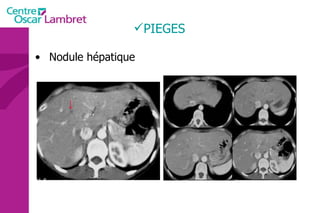

PIEGES Nodule hépatique